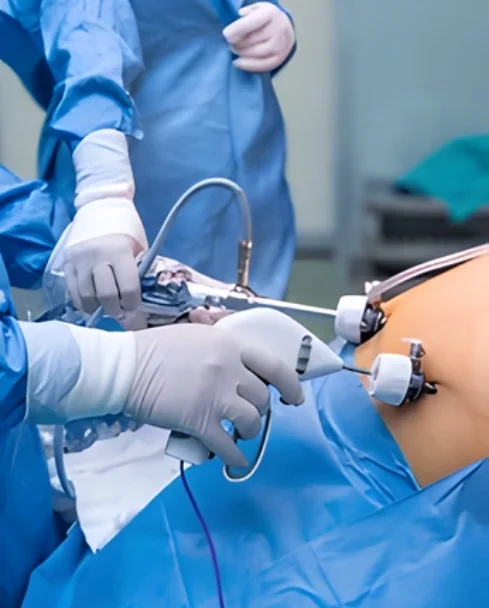

Laparoscopic and robotic oncologic procedures designed to treat cancer effectively while minimizing surgical trauma.

Minimally invasive oncologic surgery uses advanced laparoscopic and robotic techniques to remove cancer through small incisions, reducing pain, recovery time, and surgical stress on the body. When performed by a trained surgical oncologist, these procedures offer excellent cancer control with added patient comfort. Under the care of Dr. Anuj Suketu, minimally invasive cancer surgery is offered for selected patients across gastrointestinal, gynecologic, urologic, and HPB cancers. Each case is carefully evaluated to ensure that cancer safety is never compromised while delivering the benefits of modern surgical technology.

Minimally invasive oncologic procedures involve the surgical removal of cancer using small incisions, specialized instruments, and advanced visualization systems.

Laparoscopic Oncologic Surgery

Small incisions using camera-guided instruments

High-definition visualization of cancer and surrounding tissues

Reduced pain, faster mobilization, and quicker discharge

Proven oncologic safety in selected cancers